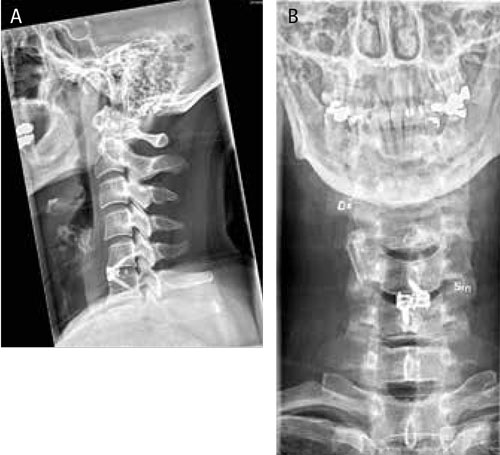

Slätröntgen efter främre cervikalryggskirurgi med diskektomi och fusion med fusionsbur, med skruvfixation i nivå C 5–C 6 i A) sagittalprojektion och B) anteroposterior projektion.